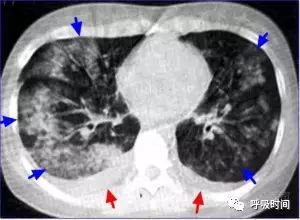

图 8 肺渗出性病变影(蓝箭头)并胸腔积液(红箭头)——病毒性肺炎